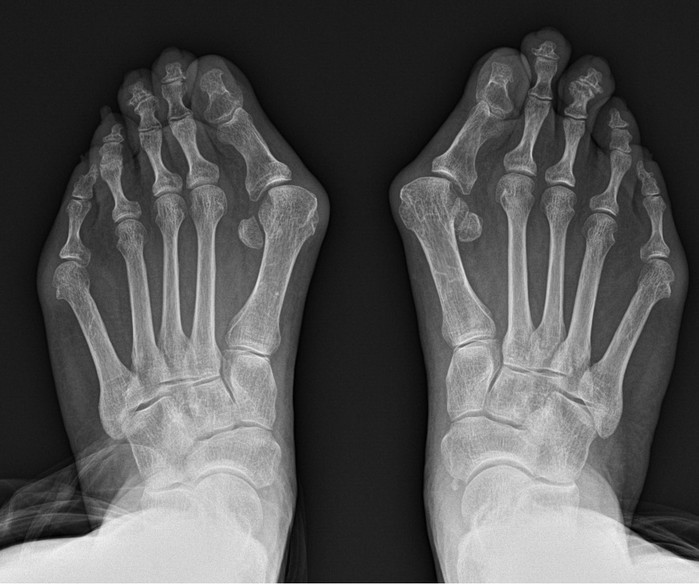

그 대표적인 예로 무지외반증을 꼽을 수 있다. 무지외반증 이란 엄지발가락이 새끼발가락 방향으로 휘며 엄지발가락이 시작되는 관절의 뼈가 돌출되는 질환이다.

무지외반증을 포함한 족부 질환 치료에 오랜 기간 매진해온 연세건우병원 박의현 병원장(정형외과 전문의)은 “무지외반증은 필연적으로 보행의 불균형을 유발한다. 정상인은 보행 시 엄지발가락에 체중의 약 60%가 실리지만 무지외반증 환자는 엄지발가락이 휘어져 있어서 그 반대로 발의 중지나 약지에 몸무게가 쏠려 정상적인 보행이 불가능해진다”고 설명한다.

이에 무지외반증 환자는 무의식적으로 엄지발가락에 체중을 싣지 않고 걷게 돼 필연적으로 발목·무릎·허리에 불필요한 스트레스가 발생, 관절·척추 질환으로 이어질 수 있다. 실제 여성 무릎관절염 환자 중 무지외반증이 동반은 비교적 흔한 편이다.

그래서 무지외반증은 되도록 빨리 치료하면 좋지만 실제로 보행에 큰 지장이 오기 전까지는 방치하는 경우가 대다수다. 오랜기간 방치하게 되면 수술이 필요하게 되는데, 발은 여러 뼈가 얽혀있는 생각보다 복잡한 부위다. 그래서 환자들은 과연 수술 후 발 모양이 정상으로 돌아올지 그리고 통증은 심하지 않은지 걱정하게 된다.

박 병원장은 돌출 부 내측 한 부위 절개를 통해 교정과정의 부담을 최소화 했다. 변형이 심하거나 양측변형 이라도 엄지뼈를 안으로 밀어 넣어 소위 ‘칼발’로 불리는 교정이 가능하다. 교정이 변형되지 않도록 수술 후 일정기간 핀이나 나사로 고정하는 것으로 수술을 마친다. 수술 과정이 축소되면서 절개창도 기존과 달리 단일화 돼 통증 및 흉터 부담도 최소침습술 만큼 경감됐다.

연세건우병원에서 밝히 지난 6년간 중증 및 양측 무지외반증 환자의 장기 추시 결과에 따르면 사고·부상 등 외상 요인을 모두 포함해도 재발률이 0.5% 미만이다. 또한 고식적인 무지외반증 수술은 통증 점수(VAS)가 7~8점이지만, 단일절개 복합교정술은 통증 점수가 2~3점에 불과하다.